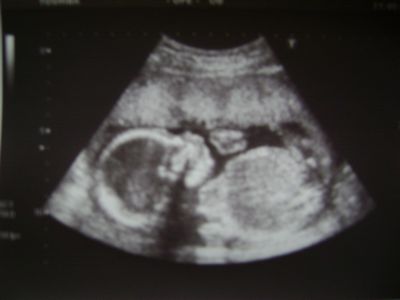

UTZ - 22.TT